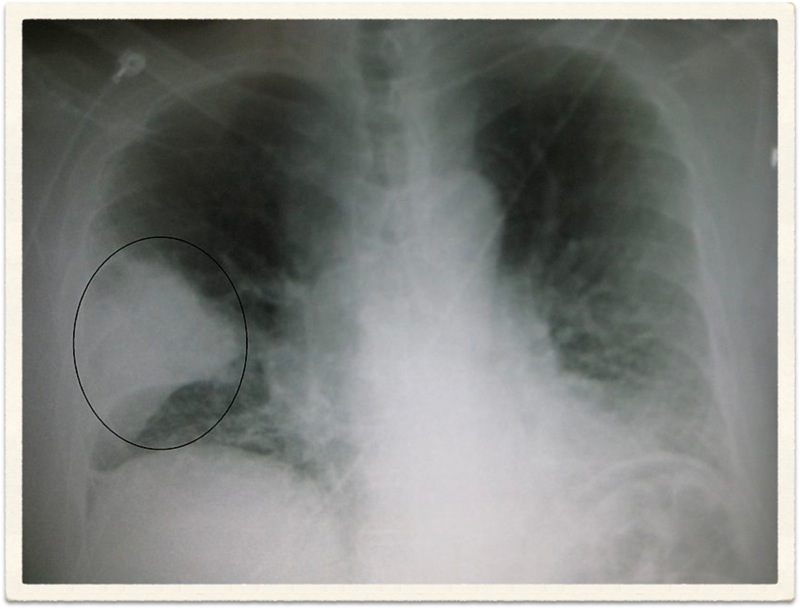

Radiological Report: Cardiac size within normal limits. Both lungs show severe overinflation typical of COPD. No sign of mass or consolidation.

Hyperinflation secondary to emphysema

Chronic bronchitis cannot be diagnosed radiologically. Although findings such as increased lung markings or tubular opacities, bronchial wall cuffing (thickening) can be seen with bronchitis, they are nonspecific. The main reason for getting a chest X-ray is to exclude other conditions, such as bronchiectasis, which can mimic the disease clinically.